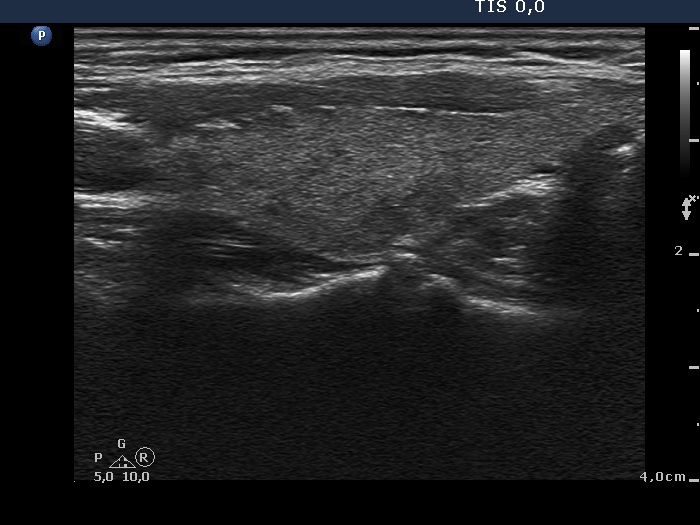

Study on 100 consecutive patients with thyroid nodule - case 006 (ultrasonographic picture 8)

Left lobe, longitudinal scan.